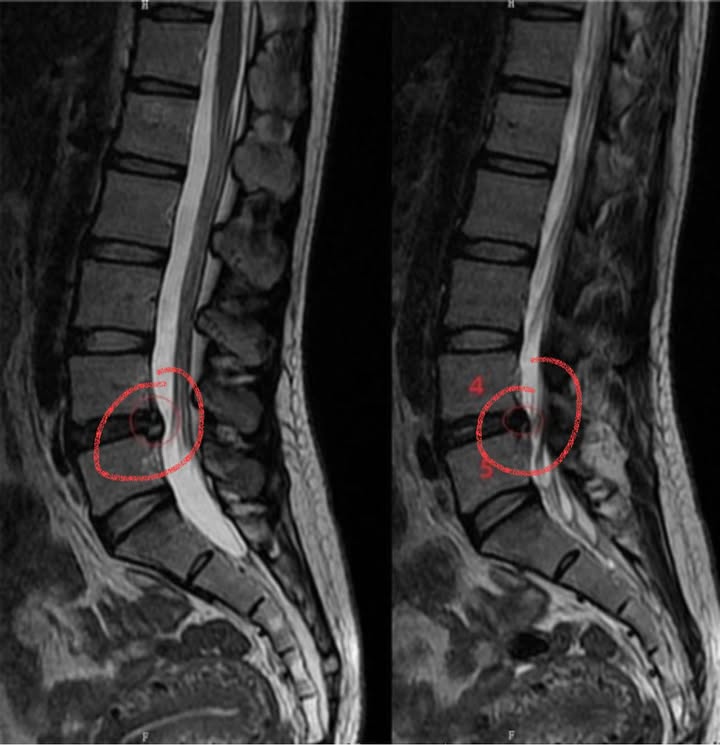

Cervical Spine Treatment Cases 腰椎治療案例 #巨大椎間盤突出一定要開刀嗎? #兩家醫學中心外科醫師說很嚴重! #有沒有辦法逆轉勝... 2021.08.10 ❖ 椎間盤突出治療醫案 ❖晨起痛爆整個人無法工作心情沮喪 😂骨科醫師說復健如果沒效可... 2022.05.12 #天才年輕賽車手巨大椎間盤突出醫案 #八周治療完全逆轉勝康復 #重新回到合法賽車場競... 2021.07.20 #腰椎滑脫痛苦不堪 #右腳麻痛無法彎腰刷牙 #感謝桃園市楊小姐熱情見證 #患者親自贈送... 2021.06.15 #巨大椎間盤突出醫案 #真的逆轉勝超感動 #三個月治療完全徹底改善 #脊刻救援成功 #徹... 2021.06.12 ⭕️L4L5巨大椎間盤突出治療醫案 🌟八週之內解除危機逆轉成功 😁順利降級成功解封印 💪... 2021.07.08 #腰椎多節椎管狹窄治療醫案 #腎臟病患者可接受中醫微創筋膜療嗎? #感謝台北市信義區張... 2021.06.01 #腰椎手術失敗綜合症候群 #感謝桃園呂伯伯熱情見證 #何時必須優先考慮再次動刀 #脊刻... 2021.07.31 #感謝新店吳先生熱情見證 #車禍後導致椎間盤突出醫案 #傳統復健六周無效痛苦不堪 #脊... 2021.05.29 #椎間盤突出治療醫案 #破紀錄三週解決 #真的逆轉勝 #感謝新莊周先生熱情見證 #脊椎整... 2021.05.26 #脊椎滑脫合併椎管狹窄醫案 #感謝台北市曹阿姨熱情見證 #之前大痛到無法走路只能拐杖... 2021.05.14 #嚴重椎管狹窄醫案導致寸步難行 #最嚴重走路無法超過十公尺 #疼痛到整個人憂鬱到不... 2021.05.07 #巨大椎間盤突出醫案逆轉勝 #感謝台北士林王先生熱情見證 #脊椎整合中醫微創療法 #原... 2021.04.29 #台灣越南國際醫療成功 #脊椎整合中醫微創療法逆轉勝 #腰椎椎間盤突出醫案 #曾經大痛... 2021.04.23 #椎間盤突出逆轉勝醫案 #原本骨科建議開刀 #脊刻救援成功 #感謝雲林患者陳小姐熱情見... 2021.04.09 ← 上一頁 7 8 9 10 11 下一頁 →